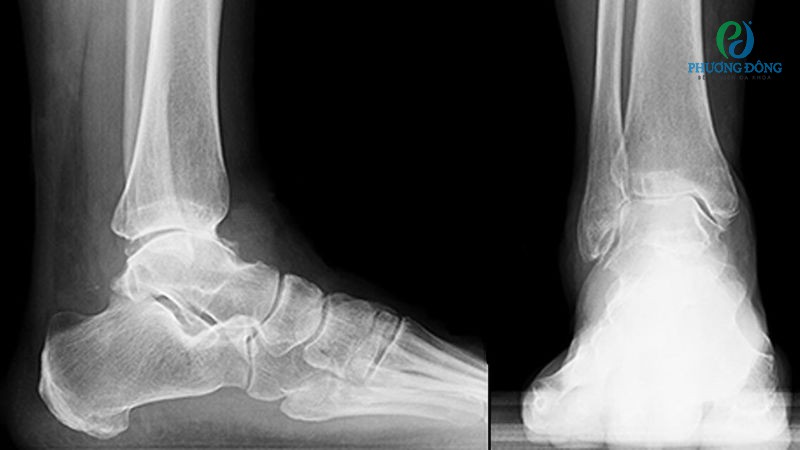

Dựa vào kết luận sơ bộ, bác sĩ sẽ chỉ định thêm các xét nghiệm cận lâm sàng như:

- Chụp X-quang giúp quan sát rõ nét cấu trúc xương và sụn khớp, tìm dấu hiệu gai xương nếu có.

- Chụp MRI cung cấp đầy đủ thông tin về sụn, khớp, hệ thống mô mềm quanh khớp, hỗ trợ công tác chẩn đoán chính xác hơn.

Phương pháp chẩn đoán nguyên nhân khiến khớp cổ chân sưng đau